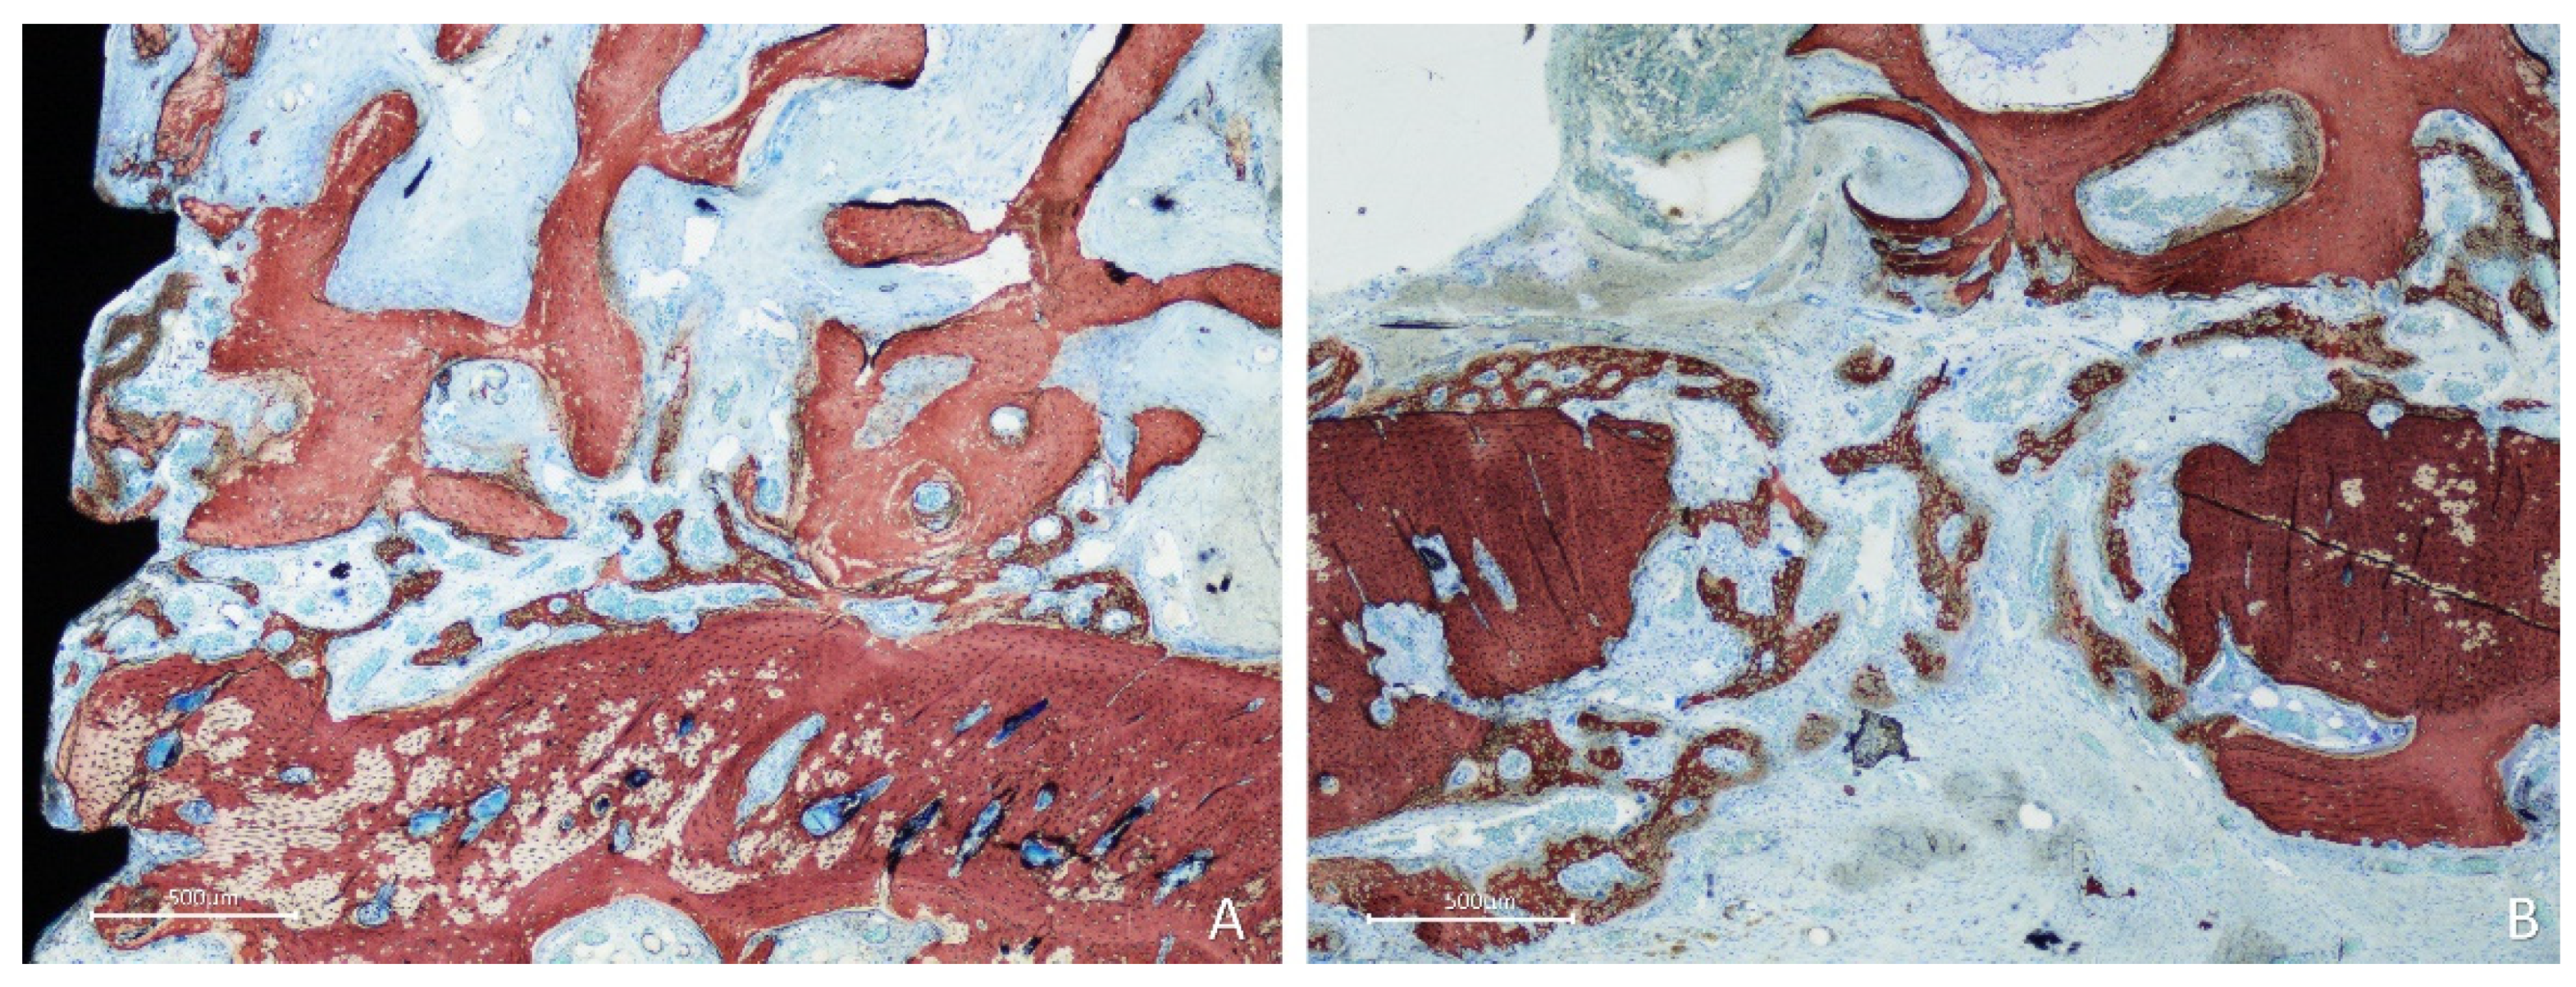

After two weeks of healing, in the onlay group, new bone was formed from the cortical layer of the lateral aspect of the mandible, interposed between the graft and parent bone, penetrating the cavities of the graft and lining onto the trabeculae (Figure 4A). Active osteogenesis was observed through cortical perforations, which contributed to bone growth (Figure 4B).

New bone was also observed forming laterally to the graft, progressing onto the outer surface of the graft (Figure 5A), from the perforation at the fixation screw (Fig. 5B), and inside the perforations created in the grafts (Figure 5C).

Figure 4. Photomicrographs of ground sections showing healing aspects at onlay graft sites after 2 weeks. A, new bone formed from the recipient site and from the perforation of the fixation screw. B, active osteogenesis through cortical perforations. Stevenel’s blue and alizarin red stain.

Figure 5. Photomicrographs of ground sections showing healing aspects at onlay graft sites after 2 weeks. New bone formed: A, laterally to the graft and from the perforations of the cortical layer; B, from the fixation screw site; C, inside a perforation created in the graft. Stevenel’s blue and alizarin red stain.